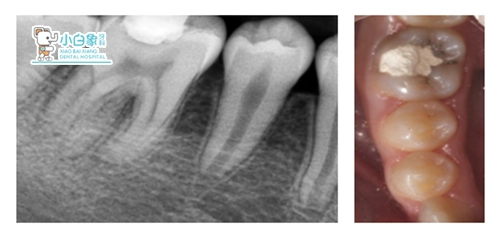

治疗计划:1. 45根治+充填全口牙周维护2.45根治+桩冠修复全口牙周维护(择期)16 17择期修复经过与患者沟通,患者选择第二种方案

治疗:45必兰麻醉下去腐,开髓揭顶,预备根管一根,根长19mm,荡洗,隔湿干燥,根充,制备桩道,树脂粘结红色纤维桩,预备全冠,扫像,设计,粘结全冠,调合。